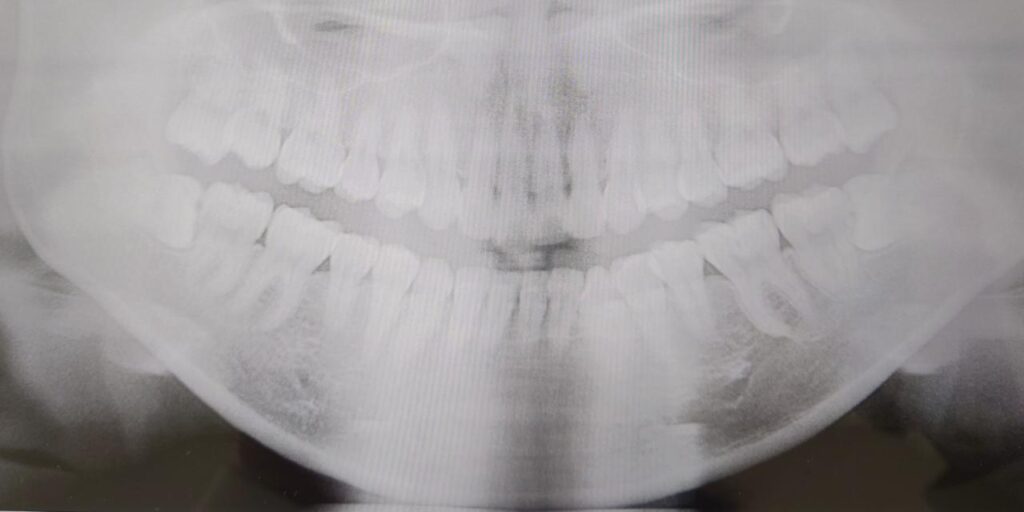

こちらは私の去年のレントゲン画像。上下左右とも1番奥に親知らずがあり、特に下の親知らずは左右とも真横を向いて少しだけ生えてる状態でした。ドクターや衛生士からは度々「抜いた方が良いよ!」と言われてました。それはなぜか……?🤔

このような親知らずは奥までブラシが当たりにくく汚れが残りやすかったり、手前の歯とぶつかっていることによって歯間の虫歯になりやすい状態でした💦

たまに痛みや腫れがあったので、これ以上悪化する前に私は左右とも抜きました!

もしかしたら私と同じような状態の親知らずをお持ちの方、いらっしゃるのではないでしょうか…?🥺